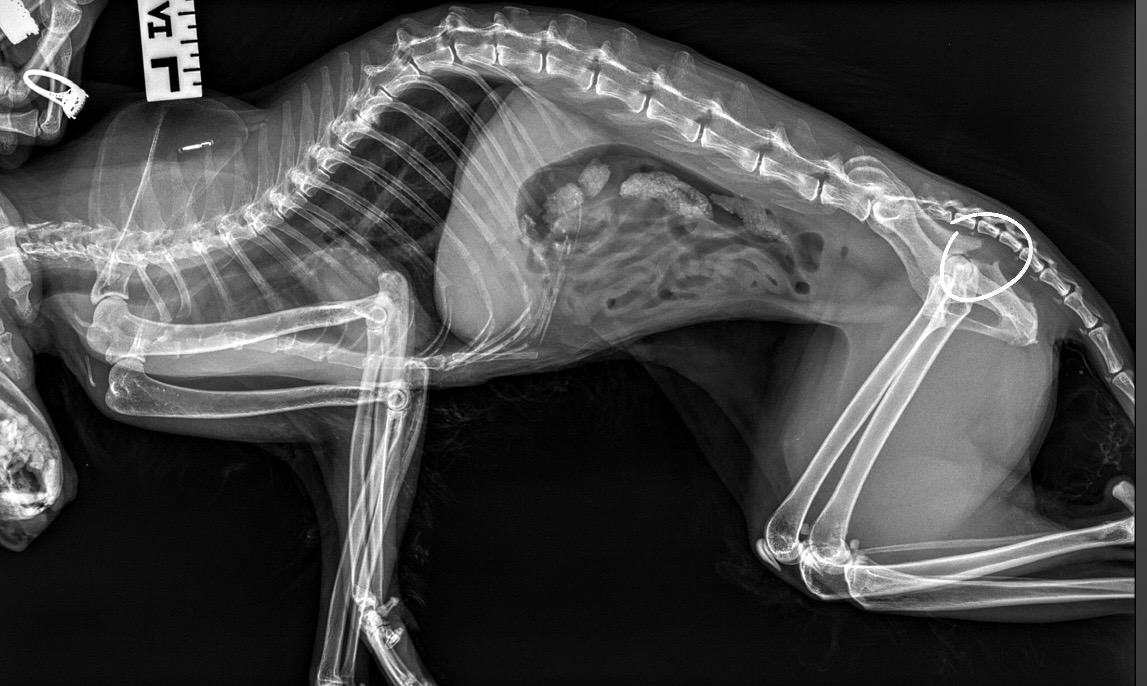

Please Help. My 17-year-old cat, Mocha, was hit by a car the morning of June 23rd, 2025, and sustained a couple of minor injuries and two major injuries. Her paw was road burned, her nose scratched up, and one side of her pelvis was broken/fractured. UPDATE: She has received the surgery but the bills are hefty . She is still eating, drinking, and attempting to find balance on her other legs to go to the bathroom, so we are confident she can recover with the right care. She is almost 18 years old but has much life in her still!